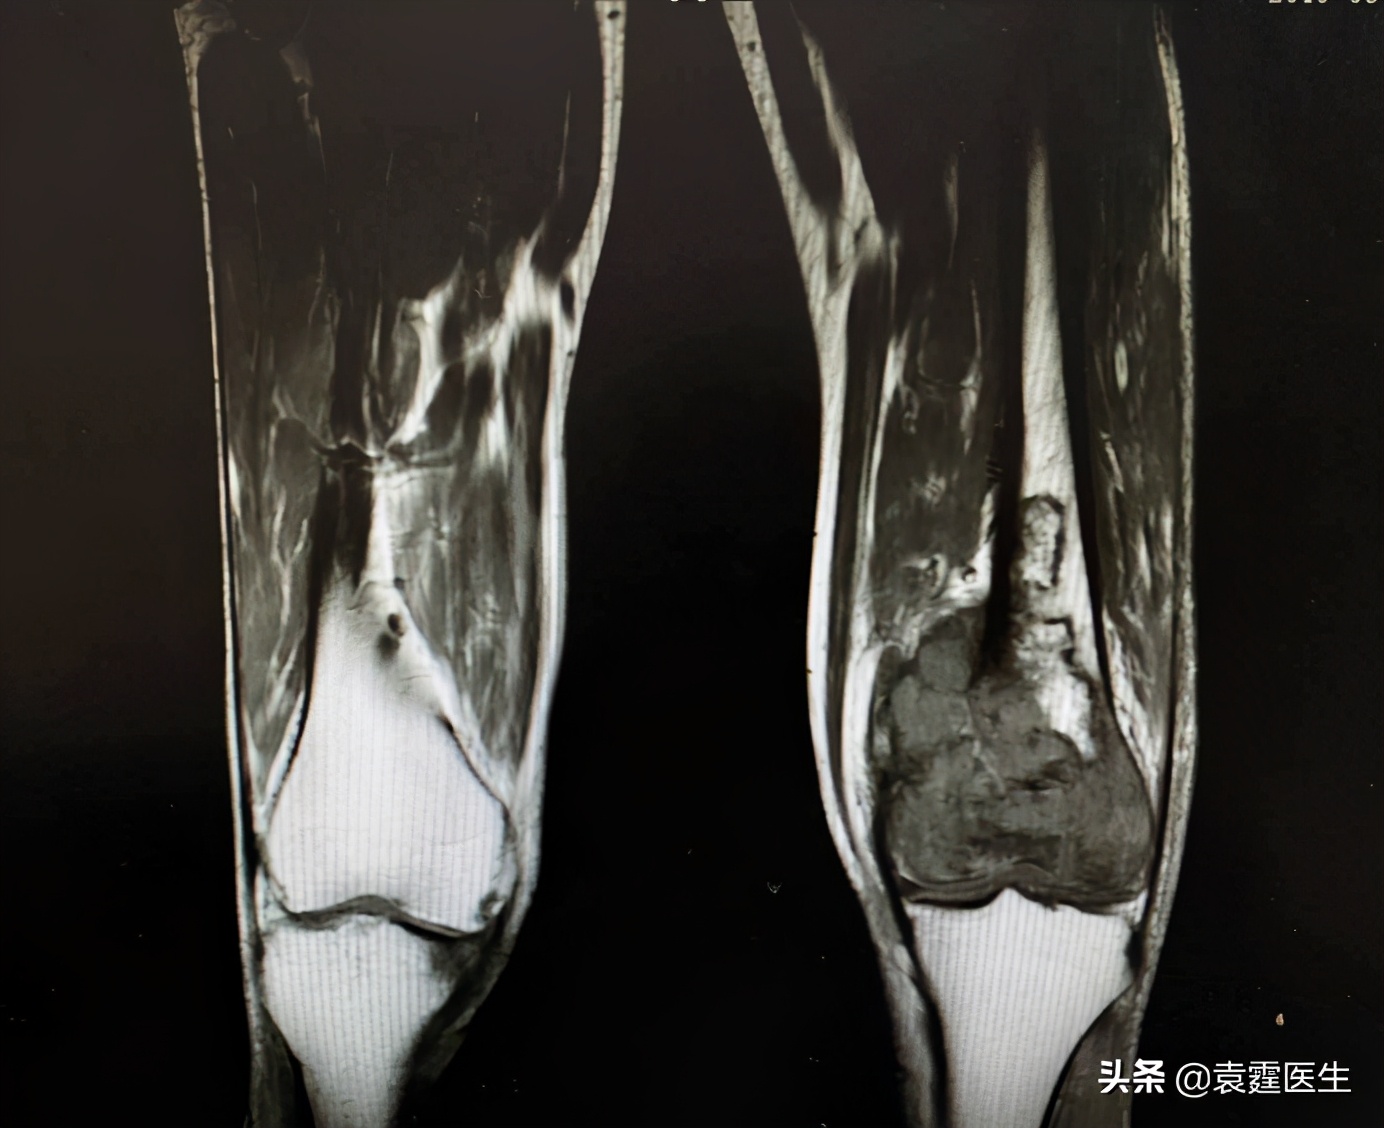

MRI

梗死相关肉瘤是罕见的。它们似乎出现在长期存在的成熟梗塞中,特别是发生在下肢的梗塞。发生梗死相关肉瘤的许多患者没有确定骨坏死发展的危险因素,但是大部分患者都有多发性骨梗死。疼痛是最常见的表现症状,在影像学上当骨质疏松和骨质破坏的骨质疏松(或矿化)区域不明确时,会出现在骨梗死的旁边。图1:X线影像学表现为股骨远端局部病变,远端骨折后。但当怀疑梗死相关肉瘤时,推荐使用图2,3:MRI来确认肉瘤的发展,并显示骨和软组织侵袭的程度,更能明确诊断,避免误诊。